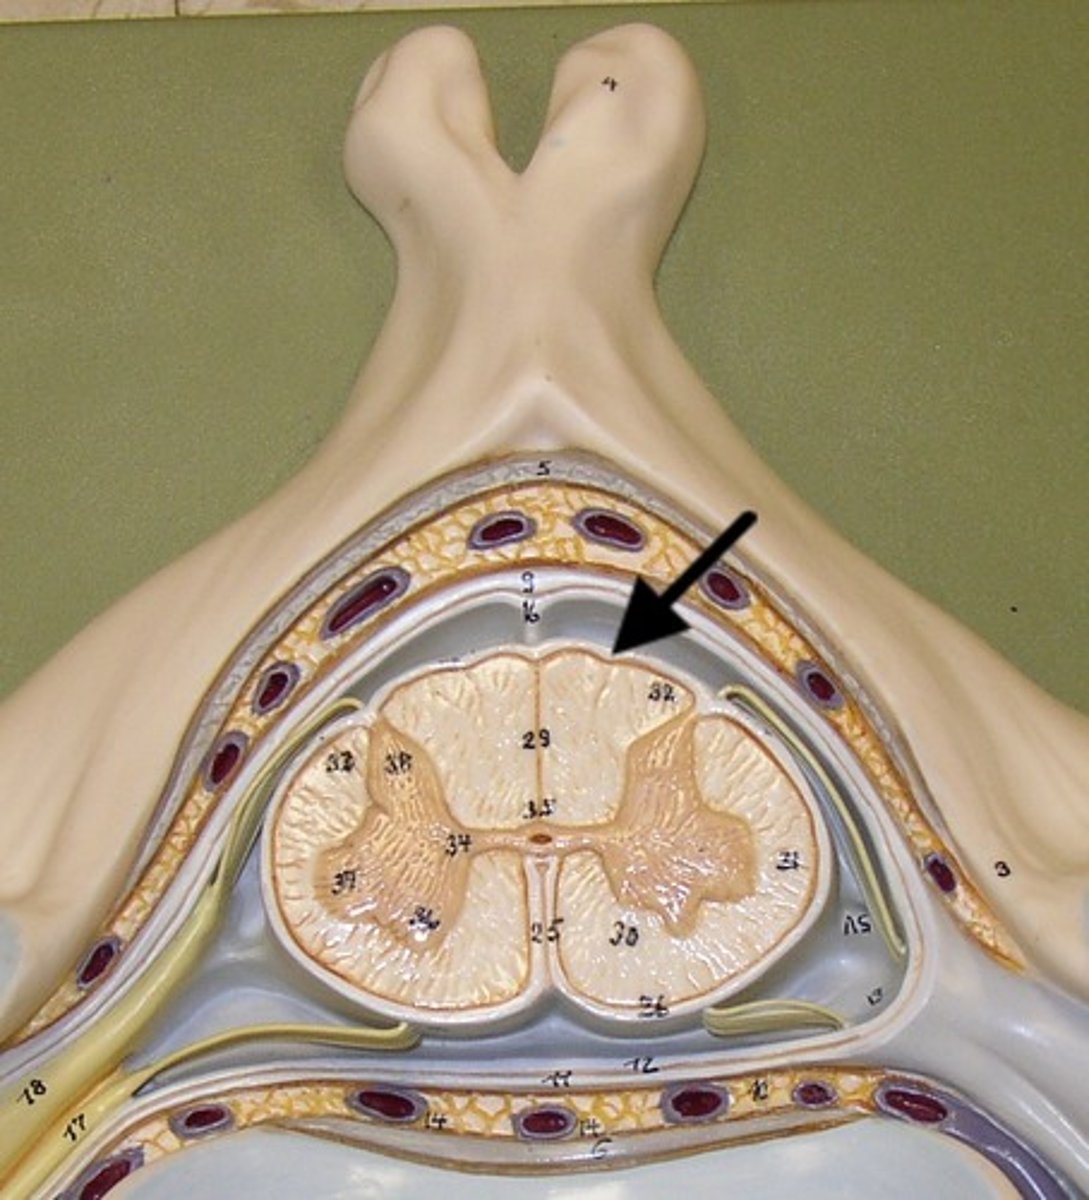

Spinal cord Anatomy (cross-sectional)

1)Internal butterfly shaped gray matter,

2)Exterior white matter,

3)Central canal filled with cerebrospinal fluid (CSF),

4)Cushioned & protected by meninges,

5)Pia mater,

6)Spinal nerves leave at the level of each vertenrae

Horns of Spinal Cord Anatomy

Dorsal Horns,

Ventral Horns,

Lateral Horns

Dorsal Horns

Lateral Horns

Ventral Horns

Interneurons

exterior white matter of the spinal cord

Ascending (sensory) and descending (motor) myelinated nerve tracts,

Posterior, anterior, lateral columns or funiculi

Posterior Columns

Anterior Columns

Lateral Columns/ funiculi

Central canal filled with what?

Central canal filled with cerebrospinal fluid (CSF)

Cushioned and protected by meninges

1) Cover the spinal cord

2) Dura mater, Arachnoid & Pia mater

dura mater of spinal cord

1) Separated from the periosteum by the epidermal space (fat, blood vessels)

2) Subdural space between dura and arachnoid mater

Dura Mater